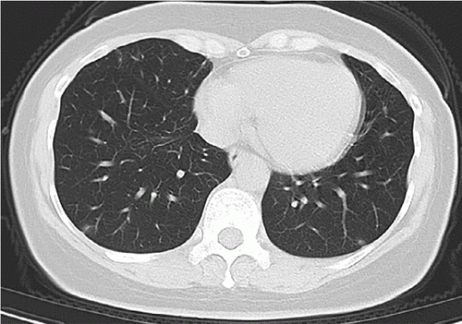

But I noticed something else in this paper too – they show us the images for some cases, and some of the images are a bit weird. The image below, which was reported to contain “atypical features of Covid-19” (specifically “small peripheral linear opacities bilaterally”), was a massive red-flag for me.

Well, they must be small, because that looks like a normal CT chest 🙂